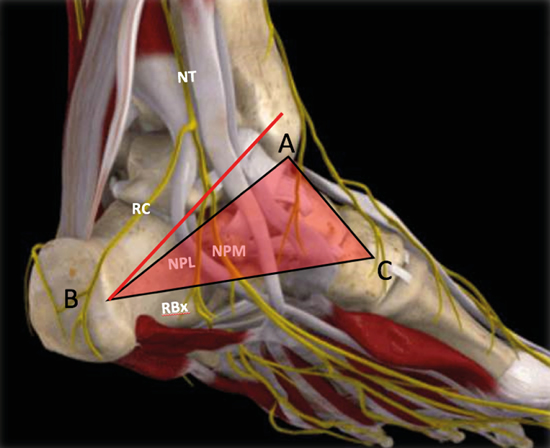

No obstante, la visualización de los nervios plantar medial y plantar lateral es más evidente cuando se avanza hacia distal. Para ello se mantiene la sonda en eje corto (Figura 13) tomando como referencia la tuberosidad posterior del calcáneo, de donde parten el eje de Dellon-Mackinnon4 y el triángulo de Heimkes (área entre tuberosidad del calcáneo, el vértice del maléolo medial y el navicular)8 (Figura 12).

Figura 12. Posición de la sonda desde el tubérculo posterior del calcáneo y sobre el vientre muscular del abductor del primer dedo.

Figura 13. Línea de Dellon-Mackinnon (A-B) y triángulo de Heimkes (A-B-C). Se observan el nervio tibial (NT) y las ramas calcánea (RC), el nervio plantar lateral (NPL), el nervio plantar medial (NPM) y la rama de Baxter (RBx). Imagen modificada de la App Ankle & Foot Pro III.